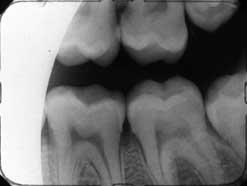

Es importante alinear el patrón de salida del haz con la película para evitar el «corte de cono». Estas dos imágenes muestran cortes de cono causados por la desalineación de conos redondos y rectangulares, respectivamente.